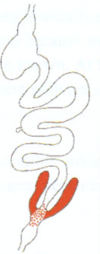

AfricanTrypanosoma sp.: life cycle

Trypanosoma equiperdum: Life cycle

Trypanosoma cruzi: Life cycle